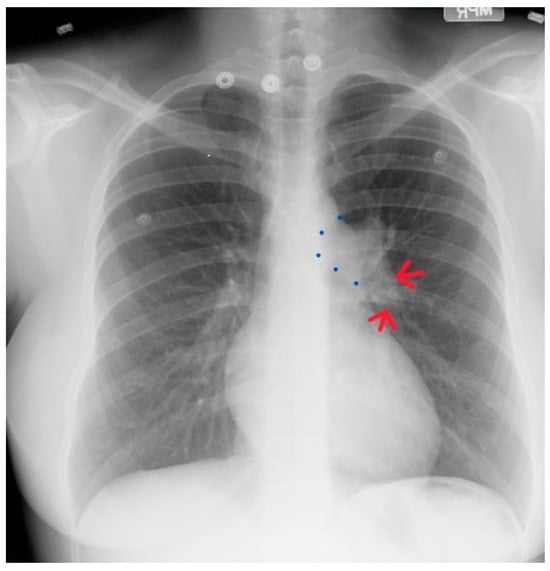

Valvular PS is usually an isolated lesion that occurs in 7–12% of all congenital heart disease cases [7]. The most common form of valvular PS features a dome-shaped pulmonary valve with a narrow central opening but a preserved, mobile valve mechanism. The pulmonary trunk is dilated and the jet from the stenotic valve favors flow to the left pulmonary artery branch. The PS gradient is categorized as mild when peak gradient is <36 mmHg, moderate when 36–64 mmHg, and severe when >64 mmHg. Valvular PS usually presents as an asymptomatic systolic murmur, but severe PS often features intolerance to exercise. Physical examination in a patient with severe PS is usually characterized by an elevated jugular venous pressure with a prominent A wave, an RV heave, and a long, loud systolic flow murmur with wide splitting of S2, if the P2 component is audible. In a study of 87 children aged 4–14 years-of-age with valvular pulmonary stenosis proven by cardiac catheterization, CXR evidence of poststenotic dilatation of the pulmonary trunk (Figure 19) and the left pulmonary artery branch, together with a normal or increased left- sided perihilar pulmonary vascularity, was essential for the diagnosis of valvular pulmonary stenosis [16]. These CXR findings of PS increased with age of the child, but no correlation between these radiographic observations and the severity of the stenosis was found. These same CXR findings are noted in the adult with valvular PS.

Figure 19.

Posteroanterior chest X-ray of severe pulmonary stenosis: this chest X-ray is of a 31-year-old female who presented with worsening exertional dyspnea over the last two years. Her exam revealed elevated jugular venous pressure with prominent A wave. She was noted to have a right ventricular lift with a grade 4/6 systolic ejection murmur best heard at the left upper sternal border. The chest X-ray is well centered and there is a good inspiration. The cardiothoracic ratio is normal. The pulmonary trunk is enlarged (its right border is outlined by blue dots as it passes over the left bronchus). The left pulmonary artery branch that is indicated by two red arrows is also enlarged. Her echocardiogram revealed severe pulmonary valve stenosis with peak gradient 68 mmHg and mild pulmonary valve regurgitation. She subsequently underwent balloon valvuloplasty with reduction of her peak gradient to 24 mmHg. Her symptoms of dyspnea had resolved a few months post-procedure.